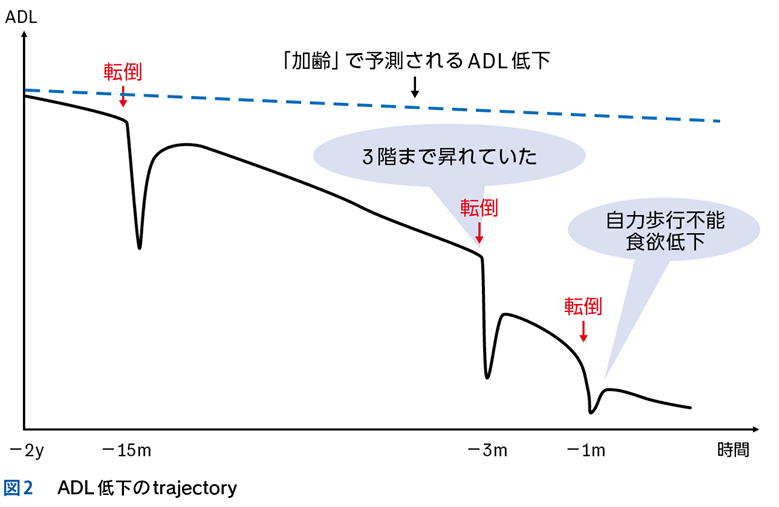

Case 1

独居の高齢者が自宅内で倒れている状態で発見され搬送された。最終健常は5日前。頻脈,SpO2低下,意識障害,感染徴候を伴う褥瘡,急性腎障害,高ナトリウム血症,クレアチンキナーゼ高値,炎症反応亢進,膿尿がみられている。

▶ この患者は何らかのイベントを契機に動けなくなり,長時間倒れていたものと推測される。多数ある「プロブレム」の中には,最初のイベントに直接起因するものもあるかもしれないが,大部分は倒れていた結果として生じてきたもの(最初のイベントの診断という観点では「ノイズ」)だろう。こういった患者が「脱水症」とか「横紋筋融解症」としてのみ治療されているケースをよく見かけるが,これは表層に現れた二次的,三次的な現象を取り上げているだけであり,最初のイベントの鑑別と治療が本来必要である。